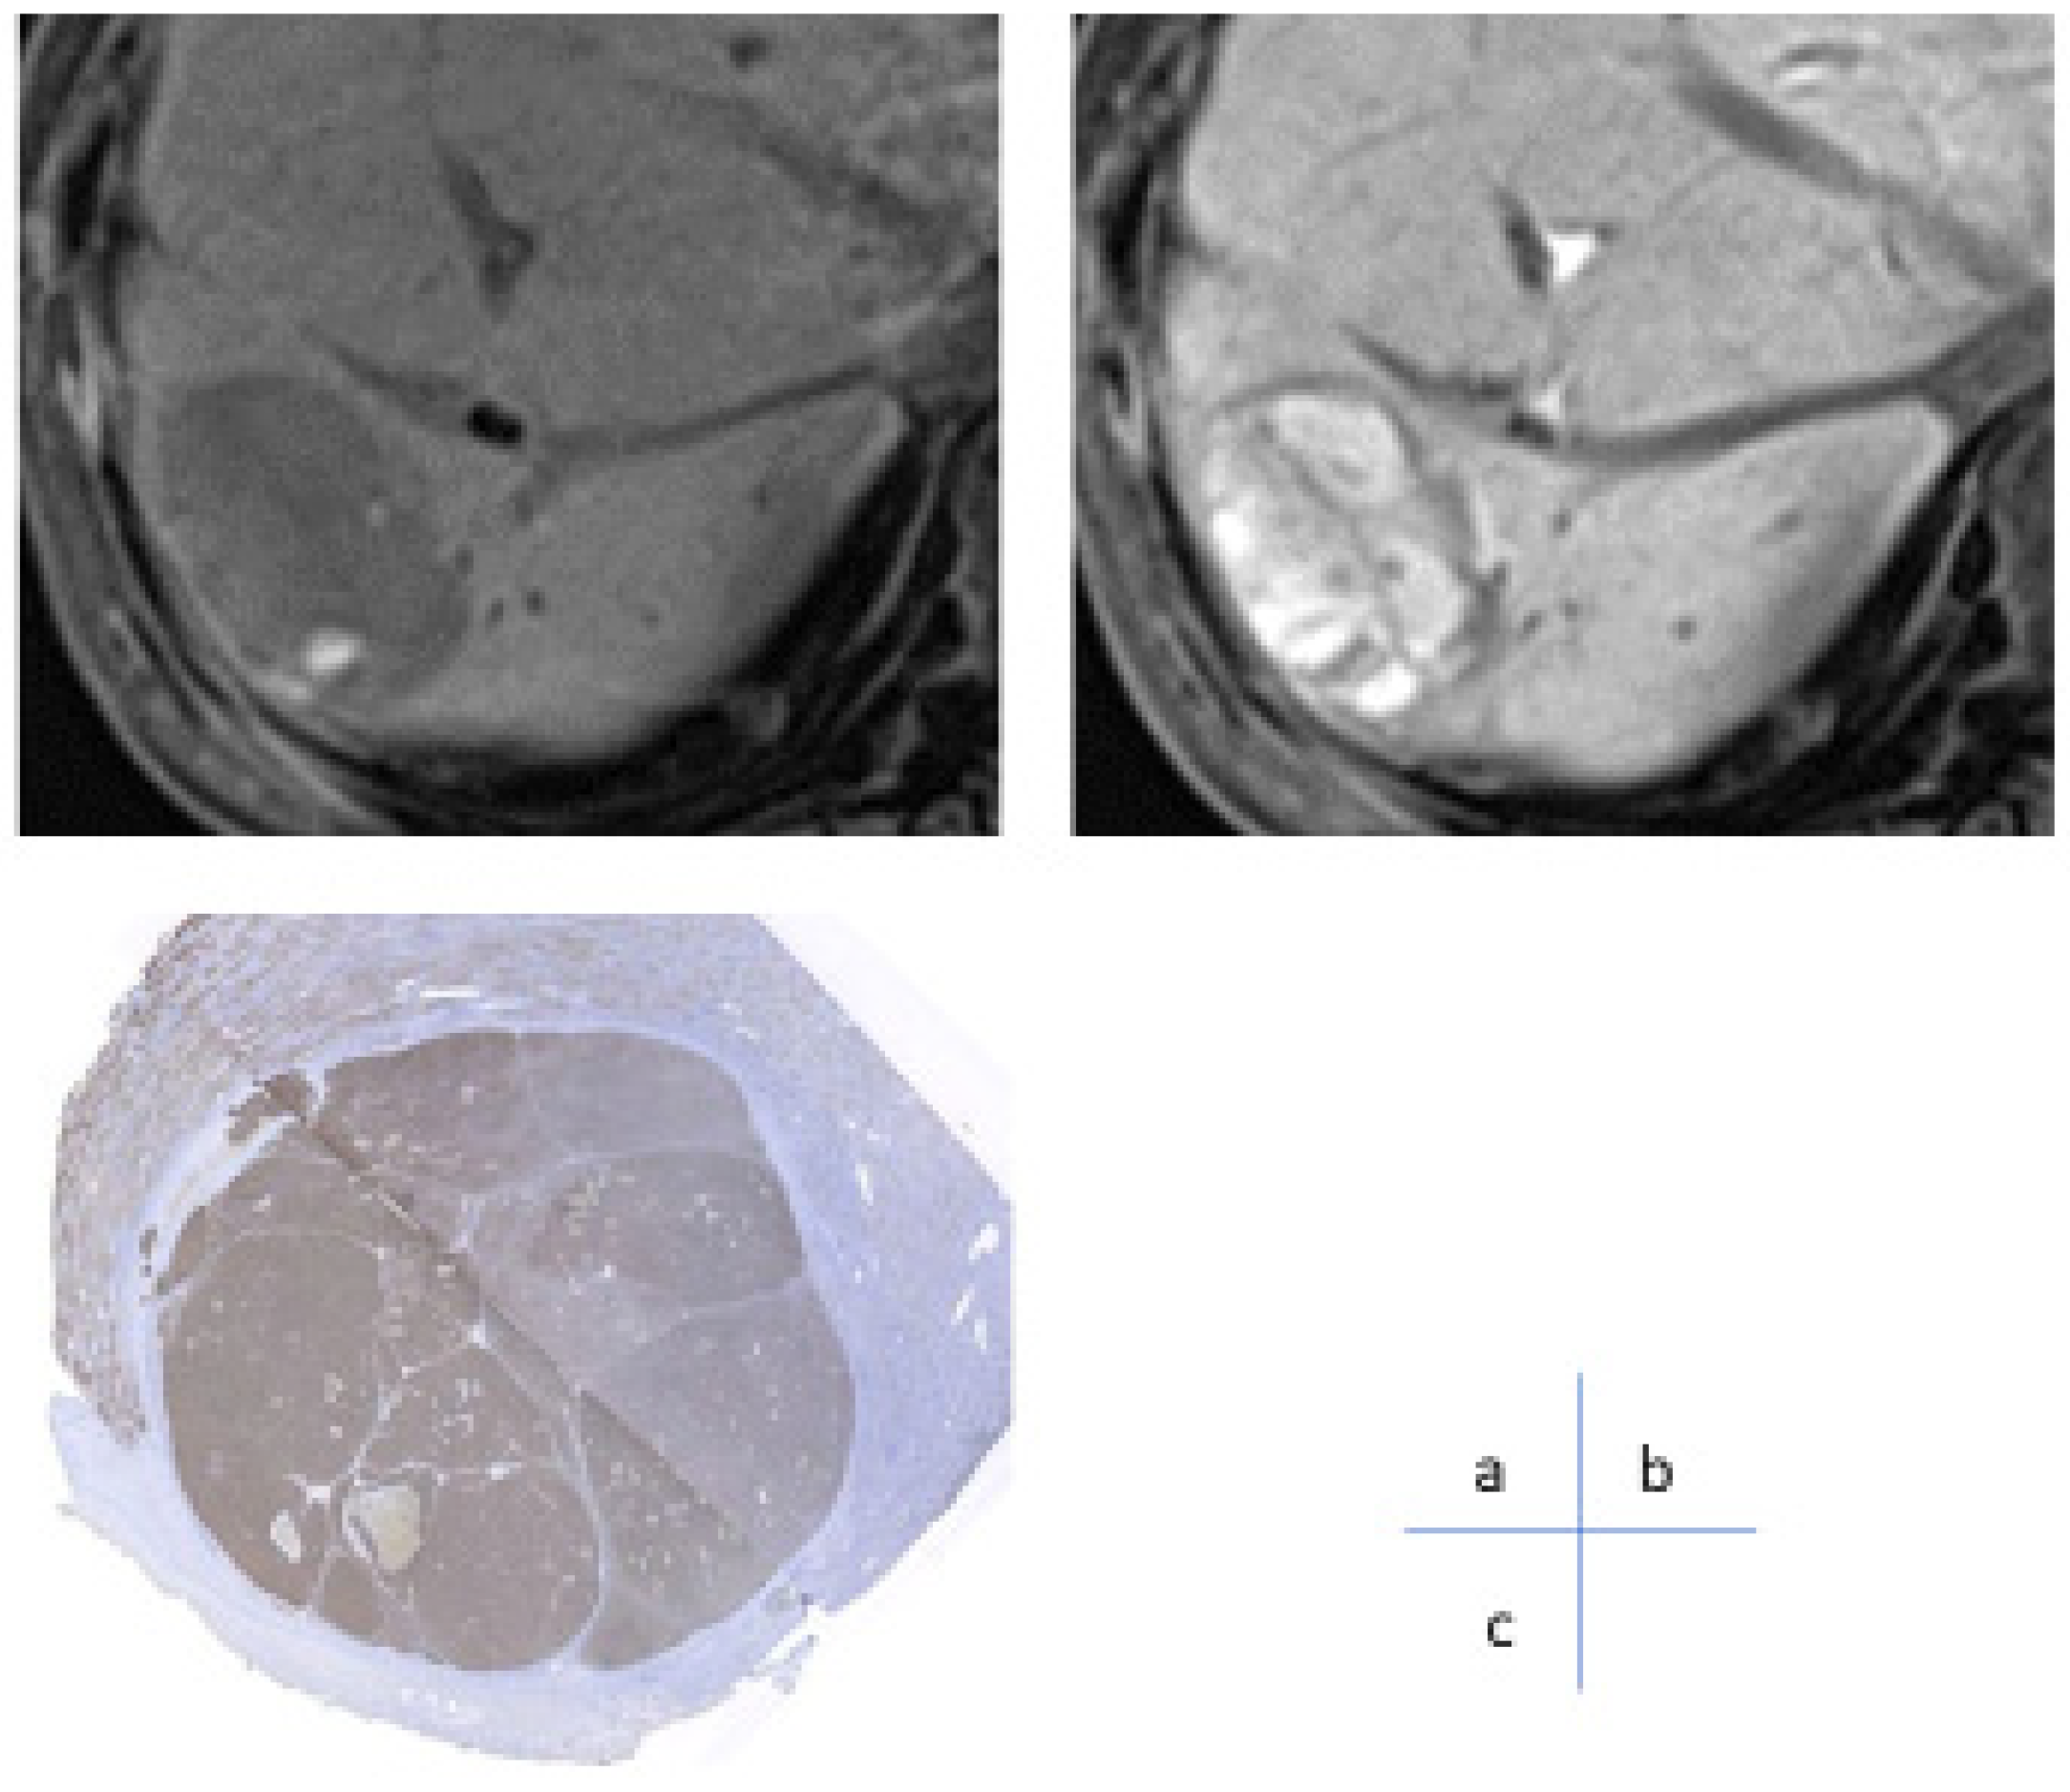

3. Role of Dynamic CT/MRI in Differentiating Tumor Grades

5. Dynamic CT/MRI Imaging for Predicting Response to Systemic Chemotherapy in HCC